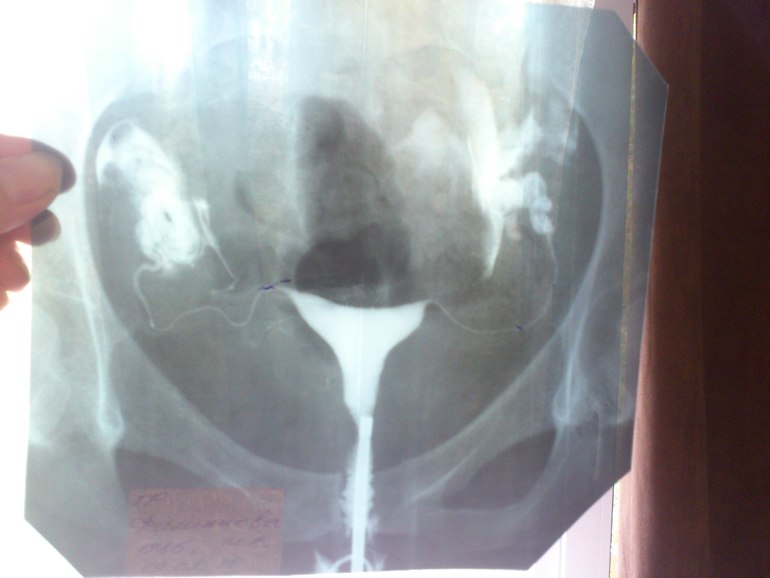

да нашли! вот она

На этом снимке ГСГ трубы проходимы но задраты высоко, как рога, а они должны окутывать яичники. Меня отправили на лапару. Когда сделали, подошла ко мне замечательный оперировавший меня врач исказала что у меня все было в спайках да и ещё припаяно все к брюшной полости! Все рассекли и поставили на место! И через 9 месяцев мы заБ! Операция была в апреле, а в январе следующего года мы заБ! Да ещё у мужа подвижность страдала ну тогда было 15% кат А, а сейчас всего 2%!